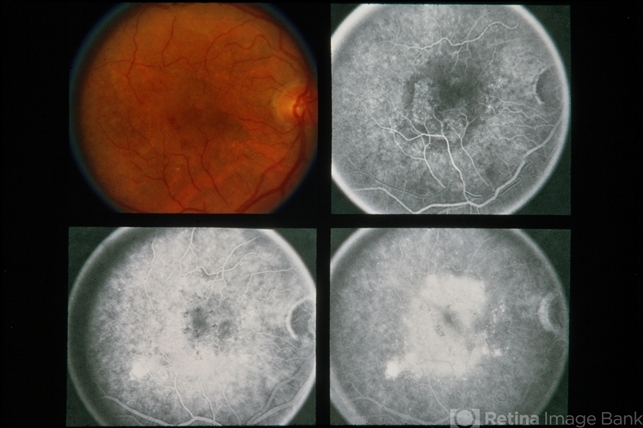

- subretinal neovascularization (SRNV)

- 70-year-old white female. SRNV-MD. 20/70-1 and 20/60-1.